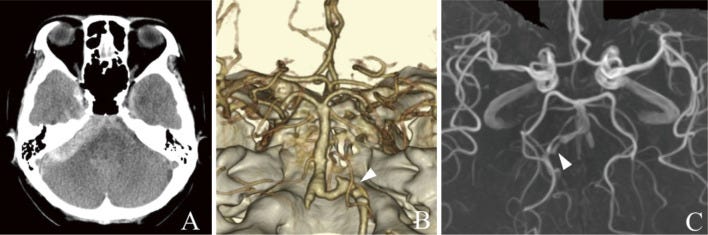

(A) Head computed tomography (CT) performed 7 days after vaccination shows massive subarachnoid hemorrhage in the posterior cranial fossa. (B) Three-dimensional CT angiography (3DCTA) performed on the same day shows a dissecting aneurysm with bleb-like protrusion on the right vertebral artery (VA). (C) Magnetic resonance angiography (MRA) performed 1 year previously shows caliber change of the right VA, retrospectively, suggesting chronic arterial dissection.